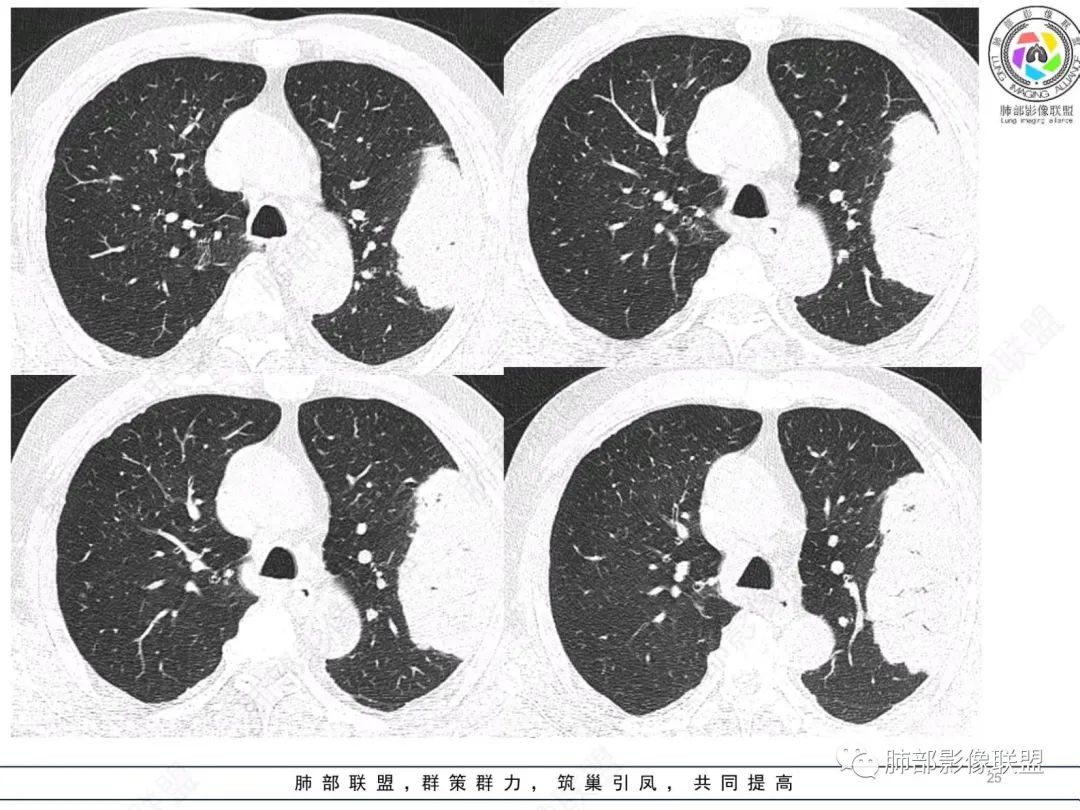

左肺上叶大肿块,膨胀性生长,边界清,密度较低,见部分坏死区,强化弱,肿块见支气管充气V扩张征,分布僵直,枯树枝特点,另一个重要特点血管造影征,淋巴瘤,肿块长轴与胸膜平行,与隐球菌鉴别,隐球荚膜抗原检查,明确诊断经皮肺穿刺。另胸膜钙化(问诊既往有无患胸膜炎病史)。

左肺上叶胸膜下肿块,宽基底与胸膜相连,跨叶裂,边缘清晰膨隆,其内支气管充气,部分扩张、僵直,无明显强化,血管造影征,考虑淋巴瘤,鉴别腺癌

左肺上叶肿块,宽基底与胸膜相连,跨叶裂,边缘清晰膨隆,可见小分叶,其内支气管充气,部分扩张、僵直,呈枯枝征,支气管达边征,增强无明显强化,可见血管造影征,考虑恶性病变,淋巴瘤,鉴别粘液腺癌。

糖尿病史,慢性病程,左肺巨大肿块,跨叶生长,肿块近端可见充气支气管征及悬浮气泡,轻度圴匀强化,病变长轴与胸膜平行,炎性标志物正常,考虑放线菌,其次淋巴瘤

支气管不像淋巴瘤,肺动脉走也不连续。支气管是断断续续的堵塞和扩张,狭窄。不是那种扩张

我再建一下血管。支气管进入,但是近端推移,堵塞

近端支气管堵塞、推移为主

内部支气管扩张

肺动脉推移为主,边缘部分进入

回头看,内部支气管近端其实不连续,伴随肺动脉不存在

还有如果从支气管的特点考虑黏膜相关性淋巴瘤,其整体应该是边缘不清楚为主,肺炎样为主。